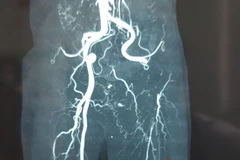

Cần Thơ: Cứu sống bệnh nhi bị dị dạng mạch máu não phức tạp hiếm gặp

Sau 5 ngày điều trị Bệnh viện Đa khoa Quốc tế S.I.S Cần Thơ, bệnh nhi H.Đ.P bị dị dạng mạch máu não phức tạp hiếm gặp, được ra viện với sức khỏe ổn định, không còn triệu chứng, không để lại di chứng.